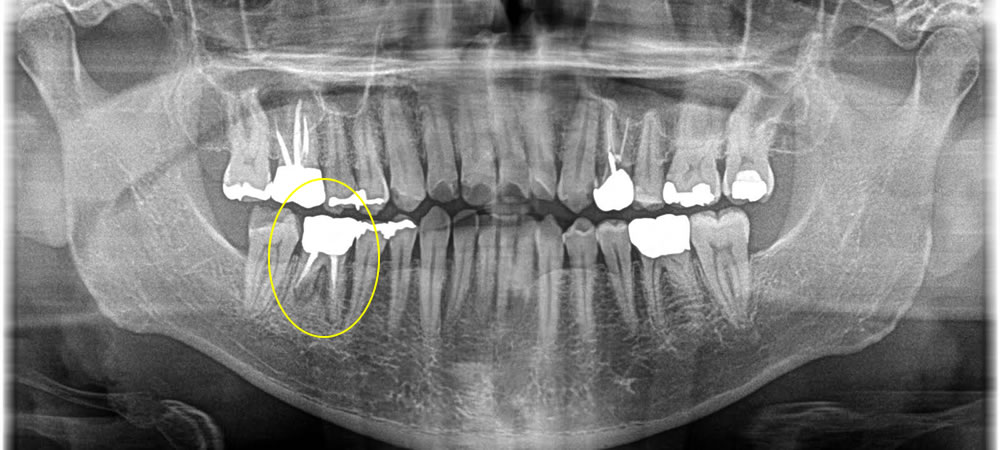

昔に根の治療を行っている歯に感染が起き、痛みが強く出ているという主訴で来院された患者さまです。患者さまと相談し、当該歯を抜歯してインプラントで治療する計画を立てました。

当該歯の下顎の骨の中には太い神経が近くにあるので、まず歯を抜いて骨を増やす処置だけを行った後、3ヵ月待ってからインプラントを埋入していきました。